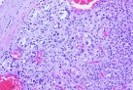

Figure 8.MEN1 syndrome enunciating an adrenocortical carcinoma with features of malignancy such as nuclear hyperplasia, hyperchromasia and pleomorphism16.